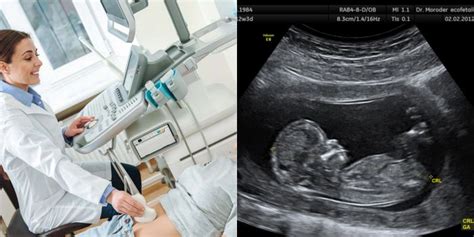

Antrasis ultragarsinis patikrinimas atliekamas 18-21 nėštumo savaitę. Jei jums to nepavyko padaryti anksčiau, dabar pats laikas.

Ultrasoundu galima įvertinti tokius parametrus:

- Vaisiaus svoris ir ūgis;

- Vaisiaus vystymosi ypatumai;

- Placentos būklė ir vieta, kraujotaka joje;

- Amniono skysčio tūris;

- Gimdos kaklelio ilgis.

Atlikdamas ultragarsą, gydytojas įvertins, ar vaisiaus ūgis ir svoris atitinka šiai nėštumo stadijai normą. Jis atidžiai išnagrinės savo vidaus organų ir nervų sistemos struktūrą ir gali nustatyti kai kuriuos vystymosi defektus. Gydytojas taip pat suskaičiuos vaisiaus širdies dūžių skaičių - įprastai jie turėtų būti 140-160 dūžių/min.

21 nėštumo savaitę ultragarsu galima nustatyti vaisiaus lytį ir sužinoti, kas gims - berniukas ar mergaitė.